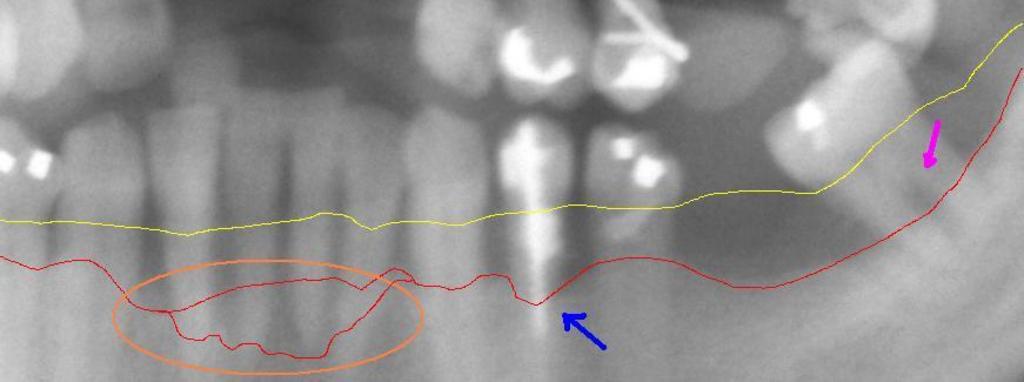

Keywords: Generalized perio -touched up.jpg en wikipedia 2009 April 27 This section from a panoramic X-ray film depicts the teeth of the lower left quadrant exhibiting generalized severe bone loss of 30 “80 The red line depicts the existing bone level whereas the yellow line depicts where the gingiva was originally 1 “2 mm above the bone prior to the patient developing periodontal disease The pink arrow on the right points to a furcation involvement or the loss of enough bone to reveal the location at which the individual roots of a molar begin to branch from the single root trunk; this is a sign of advanced periodontal disease The blue arrow in the middle shows up to 80 bone loss on tooth 21 and clinically this tooth exhibited gross mobility Finally the peach oval to the left highlights the aggressive nature with which periodontal disease generally affects mandibular incisors Because their roots are generally situated very close to each other with minimal interproximal bone and because of their location in the mouth where plaque and calculus accumulation is greatest because of the pooling of saliva mandibular anteriors suffer excessively The split in the red line depicts varying densities of bone that contribute to a vague region of definitive bone height en wikipedia Milek80 CommonsHelper 2007-08-05 DRosenbach wikipedia en DRosenbach Original upload log page en wikipedia Generalized_perio_-touched_up jpg 2007-08-05 17 28 DRosenbach 871×325× 30012 bytes <nowiki></nowiki> 2007-08-05 17 07 DRosenbach 871×325× 29601 bytes <nowiki></nowiki> Anatomy Pathology Orthopantomograms